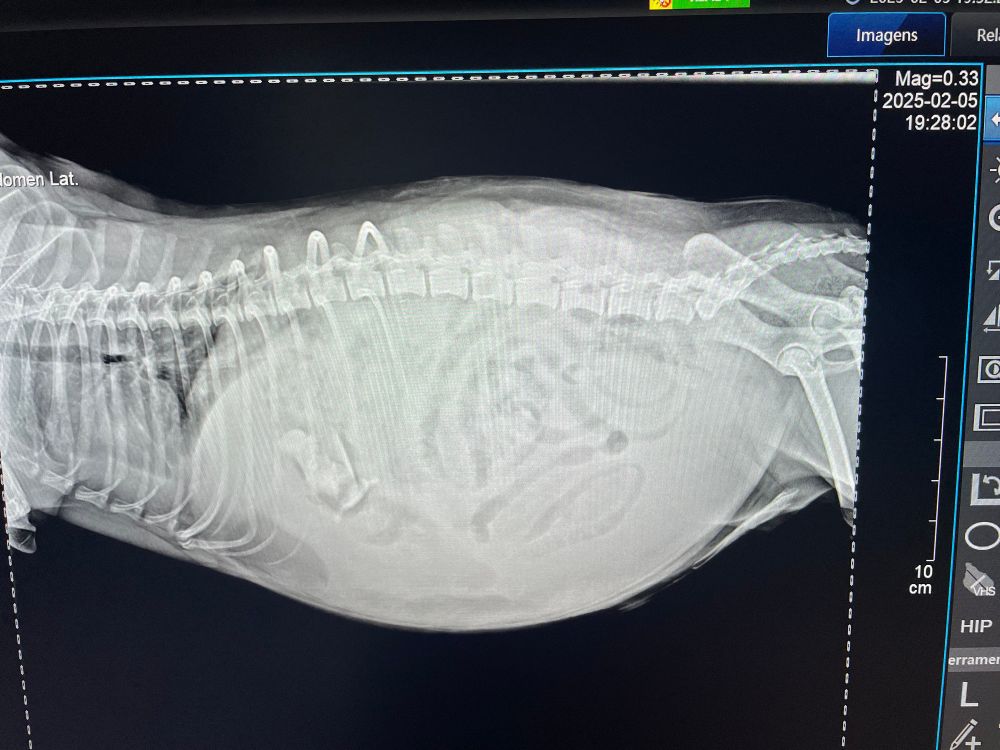

“My dog hasn’t pooped in 4 days”. Lady, this is not poop. Abdomen filled with free fluid, drained over 1.2L and let’s see what we can do with cost concerns…#veterinarymedicine

February 6, 2025 at 11:08 AM